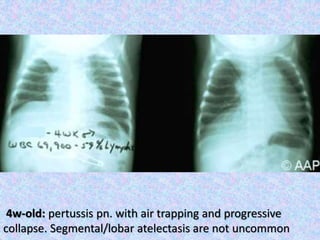

4w-old: pertussis pn. with air trapping and progressive

collapse. Segmental/lobar atelectasis are not uncommon